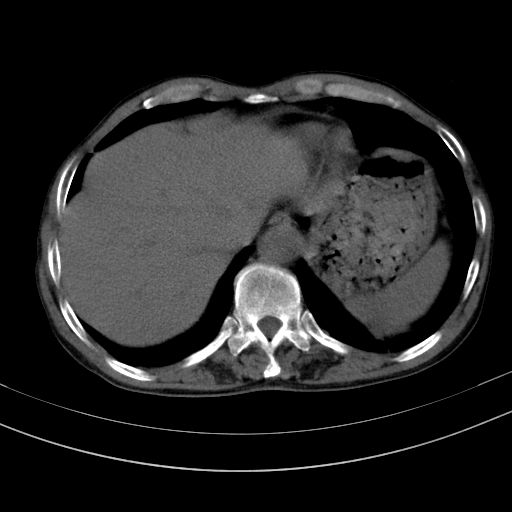

以下是引用37度在2010-1-9 14:37:00的发言:[br]1.双肾囊肿,左肾积水结石,.胆总管轻度扩张;[br]2.病灶在腹膜外,考虑纤维瘤。

以下是引用dyqct在2010-1-9 17:56:00的发言:[br]考虑:1.双肾囊肿,左肾积水结石、旋转不良。[br] 2.右侧腹直肌血肿或纤维瘤。[br]肠道准备不好。做个增强。